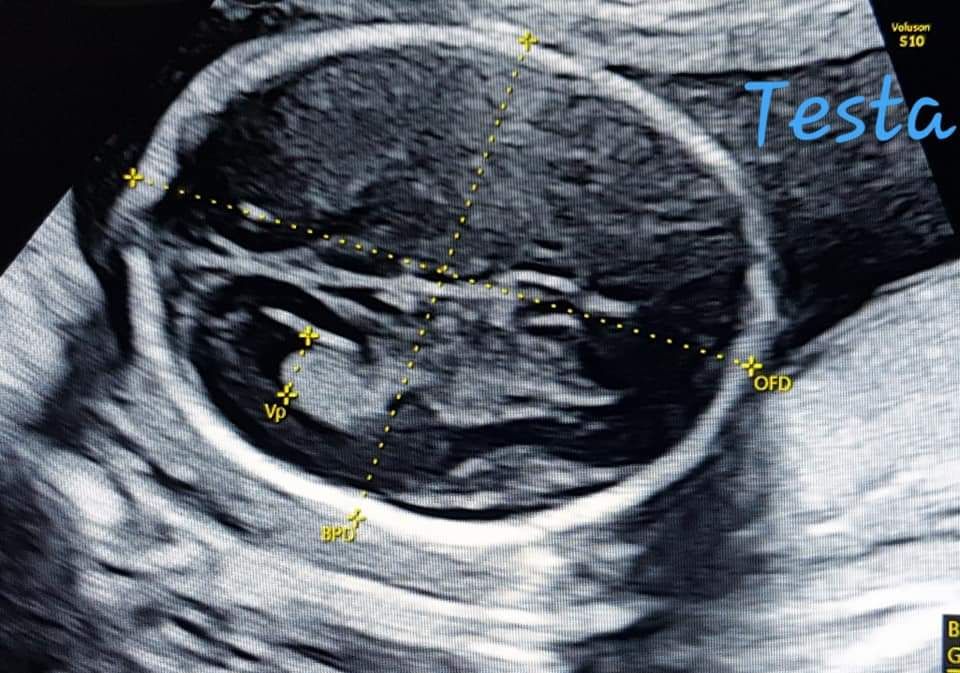

Foto e video